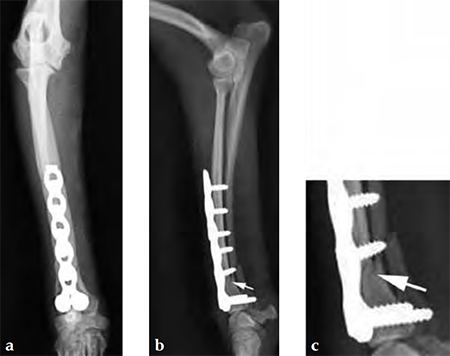

A 1-year-old female Yorkshire Terrier (1.7 kg) fractured the right distal radius and ulna (similar to a Colles fracture in humans). Open reduction and internal fixation was performed using a 7-hole 2.0 mm VET LCP notched head T-plate (a 7-hole plate was cut to eliminate the proximal two combination holes). The fracture was reduced and the distal bone fragment secured with two locking screws; the notch in the T-plate allowed independent contouring of this portion of the plate adjacent to the articulation. Compression was then applied across the fracture by loading one screw (second screw-hole proximal to the fracture); a second standard screw was then secured adjacent to the fracture (angled away/proximal to the fracture). The remaining screws were placed in a locked fashion. Despite the attempt at anatomical reduction, a slight (~1 mm) step was observed in the craniocaudal reduction (Fig 3). No fixation was applied to the ulna. A soft, padded bandage was applied to the forelimb (distal to the elbow joint) for minimal support and to control swelling.